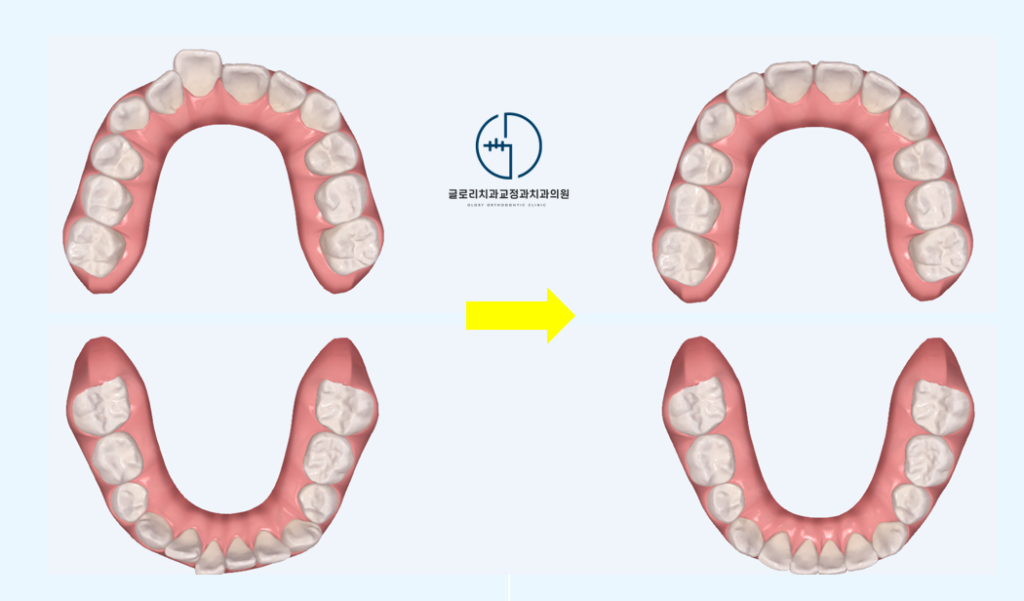

혼합치열기(유치와 영구치가 섞인 시기)에 맞춤 설계된 투명교정 장치로 치열 배열뿐만 아니라 영구치 맹출 공간 확보도 함께 유도할 수 있습니다.

그리고 일반 인비절라인과의 차이점은 아직 나지 않은 영구치 공간까지 미리 예측하여 설계한다는 점입니다.

중랑구 교정치과 에서는 클린체크 시뮬레이션을 통해 앞으로 나올 영구치 위치를 예상하고 그에 맞춰 악궁을 확장하거나 치아 배열을 유도합니다.

첫째, 악궁 확장이 가능합니다. 좁은 악궁으로 치아가 삐뚤빼뚤하게 나는 경우, 턱을 옆으로 넓혀주면서 영구치가 나올 공간을 확보해줍니다.

치료 후에는 영구치들이 본래의 자리를 되찾아 가면서 치열이 가지런하게 마무리됩니다.